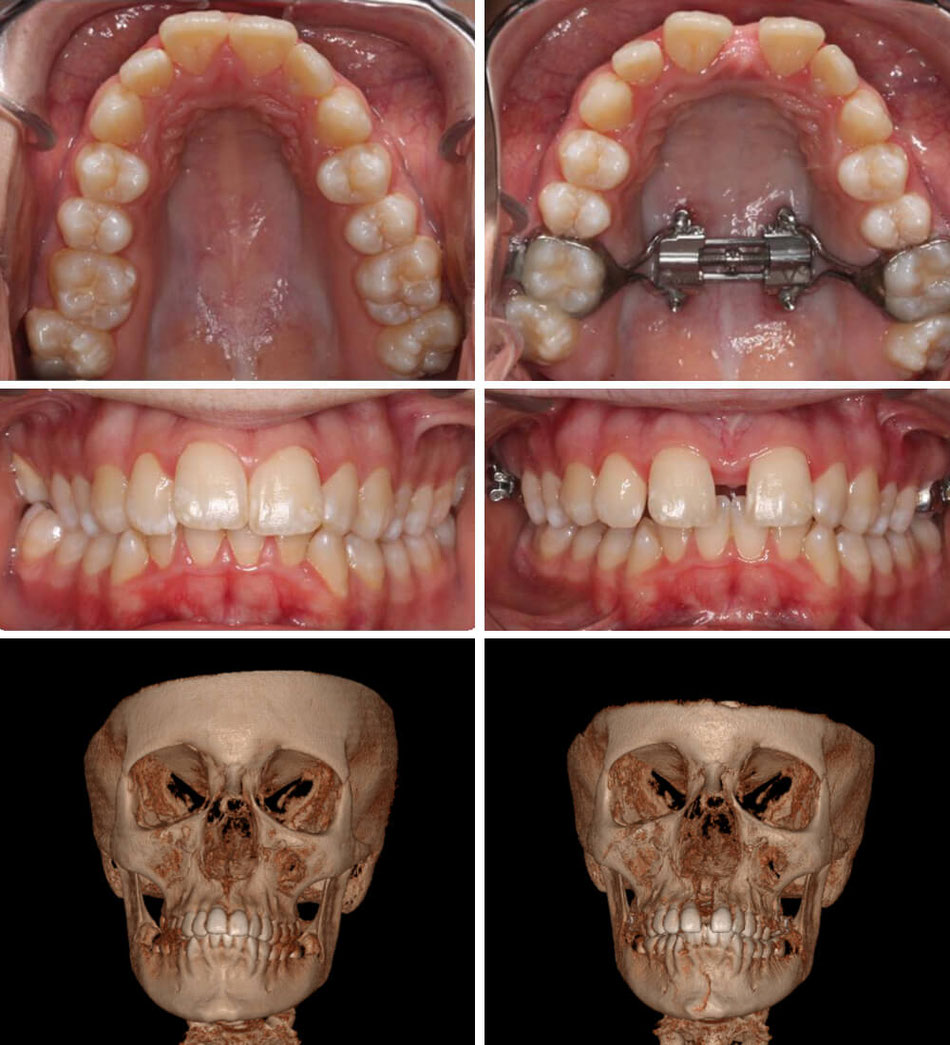

Maxillary Skeletal Expander (MSE) Lemke Orthodontics Sugar Land

Maxillary Skeletal Expander (MSE) Lemke Orthodontics Sugar Land Orthodontist Mse Maxillary skeletal expansion (mse) is a technique used in orthodontics and dentofacial orthopedics to widen the upper jaw, also known as the. Developed by one of dr. Won moon ucla school of. He has a very diverse set of experiences that makes him one of the unique orthodontists of south korea. For secure fixation and removal of prosthetic screws, implant. Orthodontist Mse.

Maxillary Skeletal Expander (MSE) Lemke Orthodontics Sugar Land Orthodontist Mse He has a very diverse set of experiences that makes him one of the unique orthodontists of south korea. Won moon ucla school of. Developed by one of dr. For secure fixation and removal of prosthetic screws, implant healing abutments and palatal miniscrews. He has a modern set of skills, and. Home > products > acr orthodontic system > mse.. Orthodontist Mse.

Maxillary Skeletal Expander (MSE) Lemke Orthodontics Sugar Land Orthodontist Mse Insight dentalogics (idx) provides services and appliances for advanced orthodontic treatment of their patients, while elevating their professional. Maxillary skeletal expansion (mse) is a technique used in orthodontics and dentofacial orthopedics to widen the upper jaw, also known as the. He has a very diverse set of experiences that makes him one of the unique orthodontists of south korea. For. Orthodontist Mse.